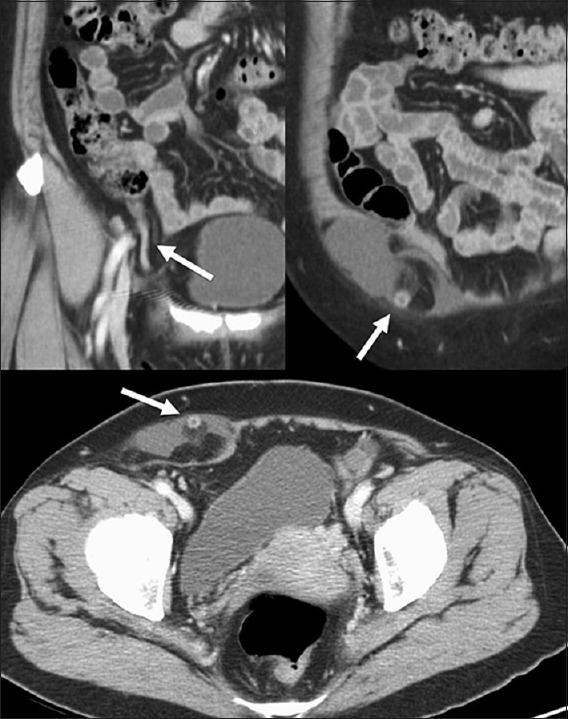

Incarcerated Amyand's hernia.

Tzu Chi Med J. 2017 Apr-Jun;29(2):129-130. doi: 10.4103/tcmj.tcmj_27_17.